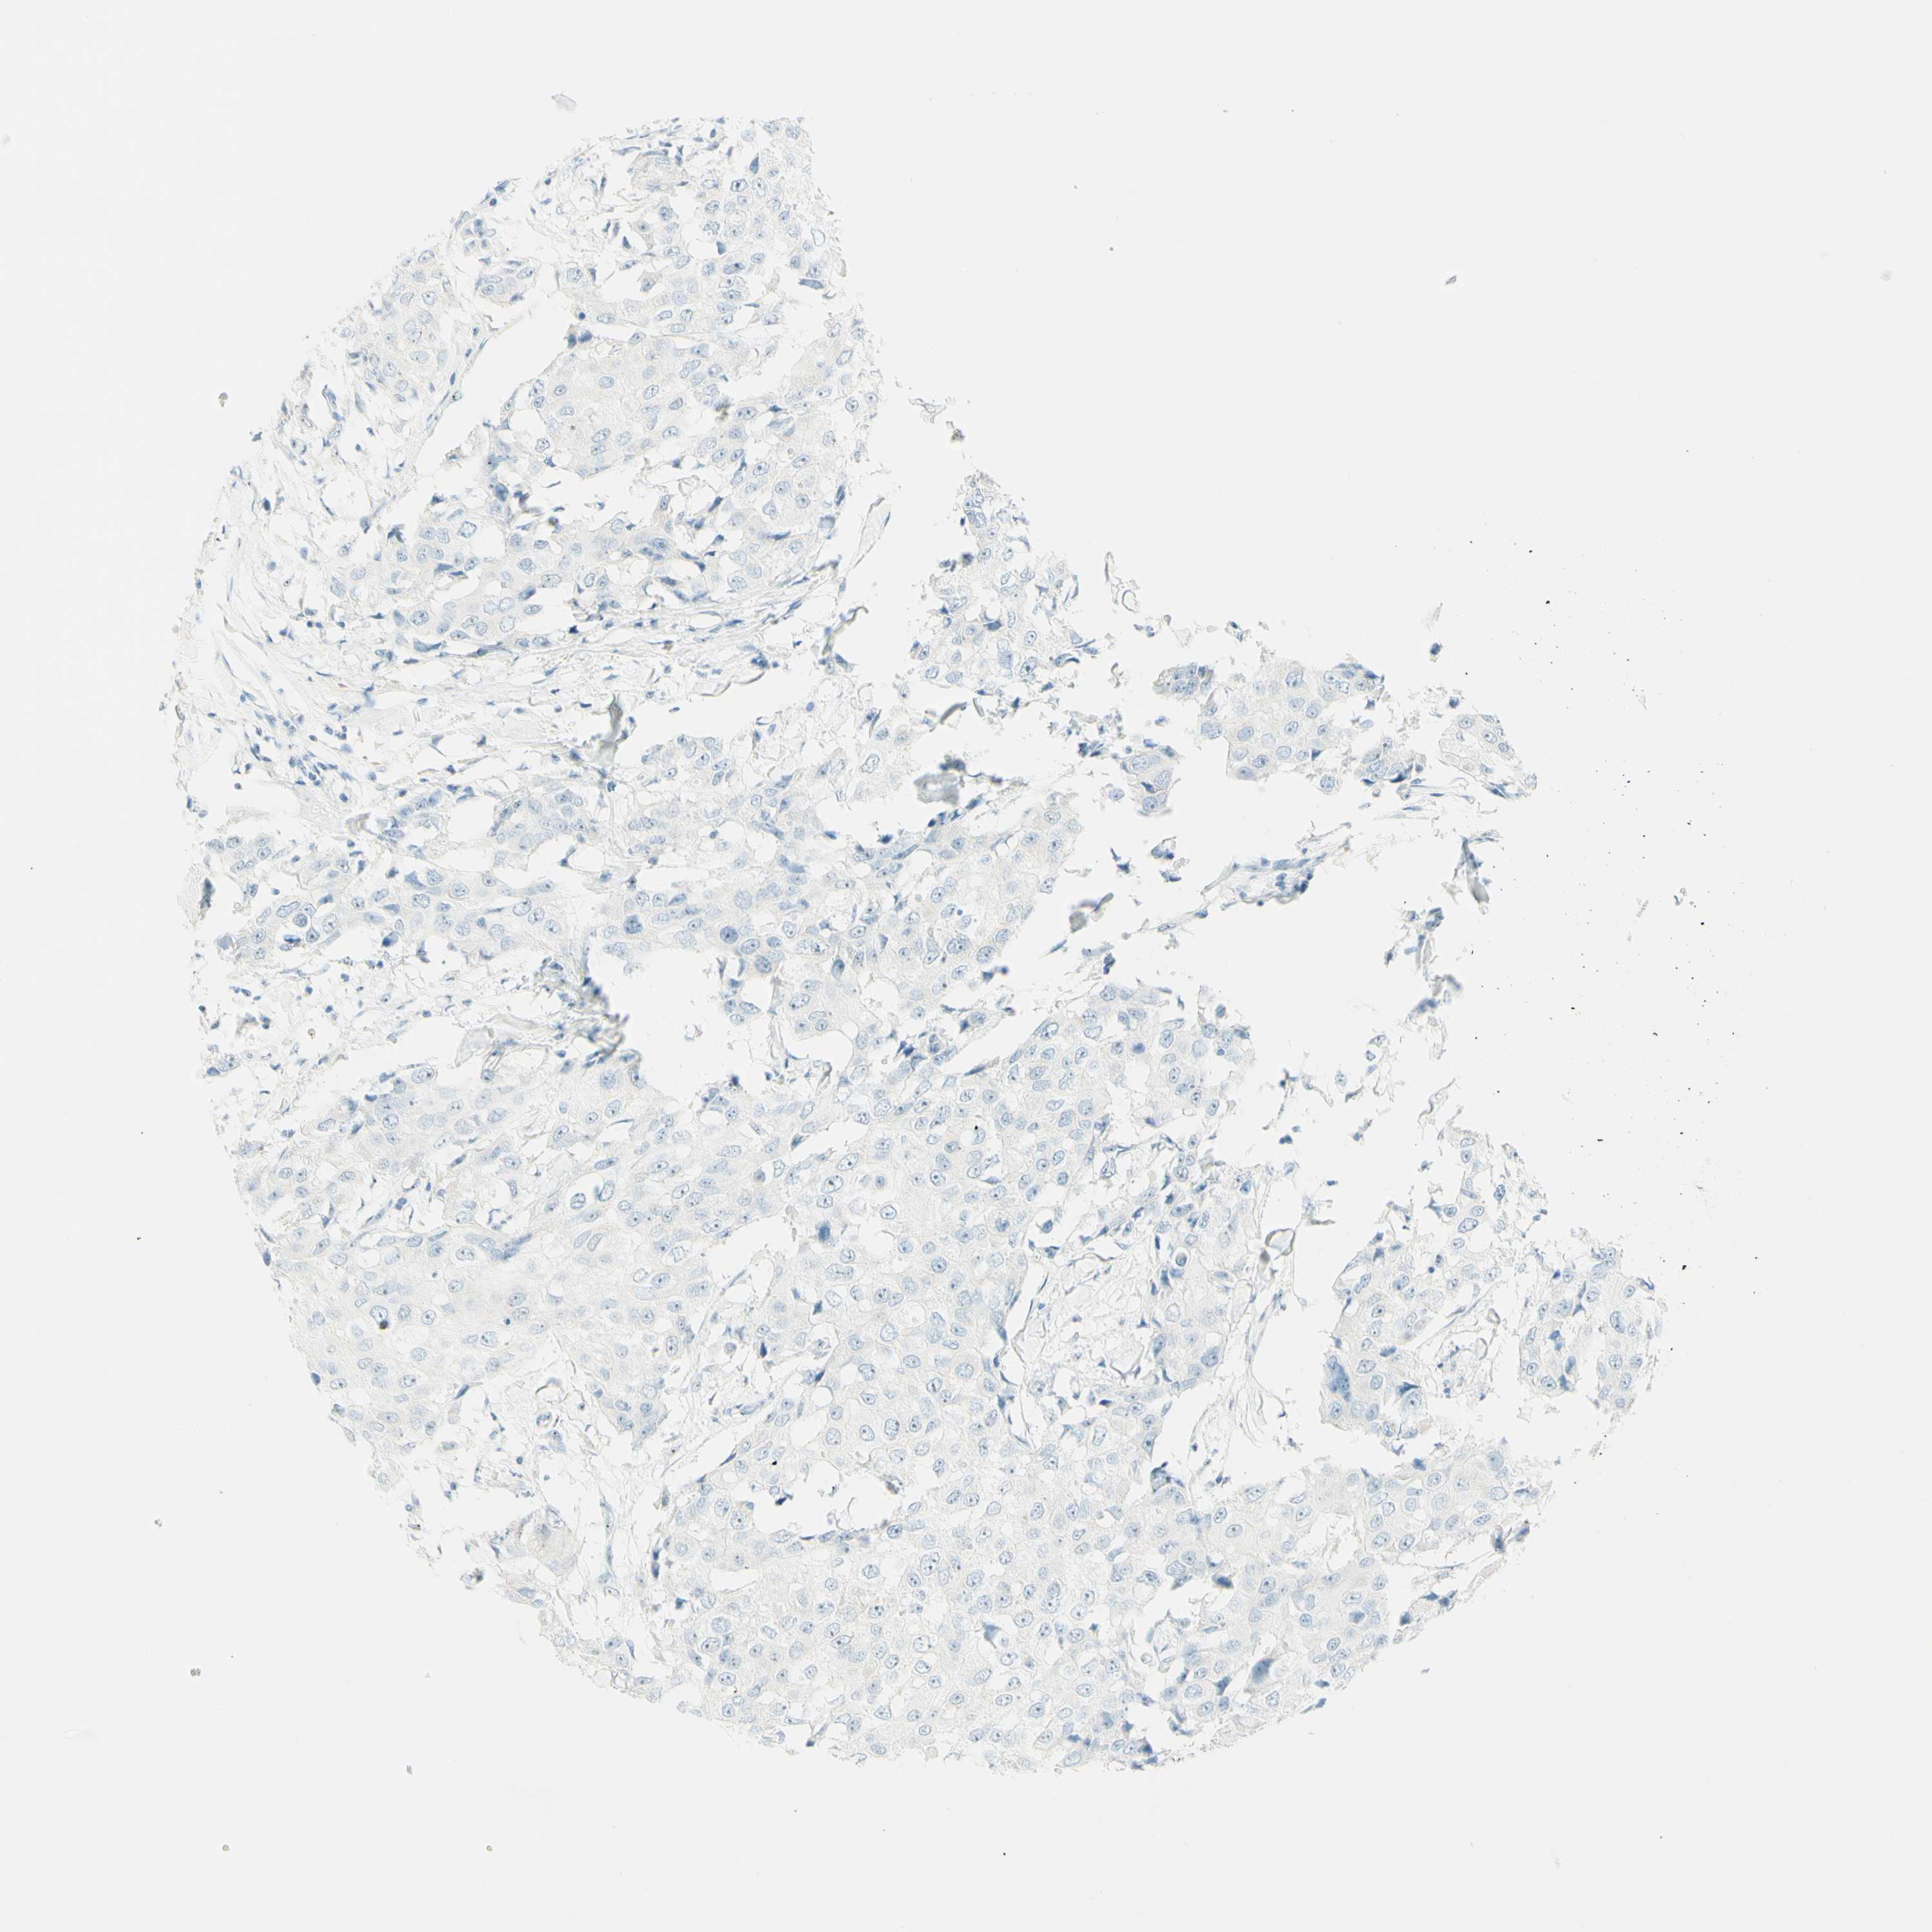

BRCA TCGA BRCA VALIDATION PROTEIN EXPRESSION